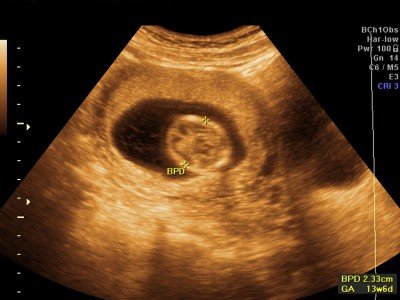

Těhotenská kalkulačka

V naší těhotenské kalkulačce si můžete spočítat týden těhotenství, trimestr, předpokládaný termín porodu, počet dní do termínu porodu a odhad váhy a délky miminka.